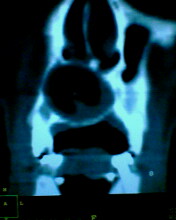

患者:男71岁,右侧上颚肿物无痛性生长7年.

右上颌骨近中线部见类圆形低密度区,上方见一液平,周围见一薄硬化环,前下方见一牙根,后方累及水平板。上方突入鼻腔前下部,下方突入口腔。

考虑:右侧上颌骨囊肿伴感染。